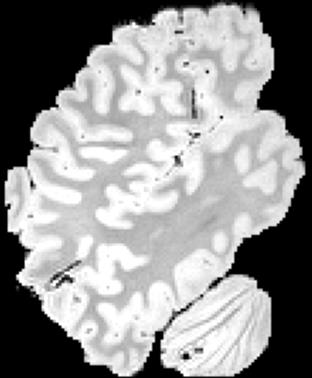

In neuroimaging, MRI tissue properties characterize underlying neurobiology, provide quantitative biomarkers for neurological disease detection and analysis, and can be used to synthesize arbitrary MRI contrasts. Estimating tissue properties from a single scan session using a protocol available on all clinical scanners promises to reduce scan time and cost, enable quantitative analysis in routine clinical scans and provide scan-independent biomarkers of disease. However, existing tissue properties estimation methods - most often $\mathbf{T_1}$ relaxation, $\mathbf{T_2^*}$ relaxation, and proton density ($\mathbf{PD}$) - require data from multiple scan sessions and cannot estimate all properties from a single clinically available MRI protocol such as the multiecho MRI scan. In addition, the widespread use of non-standard acquisition parameters across clinical imaging sites require estimation methods that can generalize across varying scanner parameters. However, existing learning methods are acquisition protocol specific and cannot estimate from heterogenous clinical data from different imaging sites. In this work we propose an unsupervised deep-learning strategy that employs MRI physics to estimate all three tissue properties from a single multiecho MRI scan session, and generalizes across varying acquisition parameters. The proposed strategy optimizes accurate synthesis of new MRI contrasts from estimated latent tissue properties, enabling unsupervised training, we also employ random acquisition parameters during training to achieve acquisition generalization. We provide the first demonstration of estimating all tissue properties from a single multiecho scan session. We demonstrate improved accuracy and generalizability for tissue property estimation and MRI synthesis.